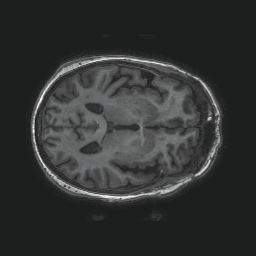

Model-based treatment planning for transcranial ultrasound therapy typically involves mapping the acoustic properties of the skull from an x-ray computed tomography (CT) image of the head. Here, three methods for generating pseudo-CT images from magnetic resonance (MR) images were compared as an alternative to CT. A convolutional neural network (U-Net) was trained on paired MR-CT images to generate pseudo-CT images from either T1-weighted or zero-echo time (ZTE) MR images (denoted tCT and zCT, respectively). A direct mapping from ZTE to pseudo-CT was also implemented (denoted cCT). When comparing the pseudo-CT and ground truth CT images for the test set, the mean absolute error was 133, 83, and 145 Hounsfield units (HU) across the whole head, and 398, 222, and 336 HU within the skull for the tCT, zCT, and cCT images, respectively. Ultrasound simulations were also performed using the generated pseudo-CT images and compared to simulations based on CT. An annular array transducer was used targeting the visual or motor cortex. The mean differences in the simulated focal pressure, focal position, and focal volume were 9.9%, 1.5 mm, and 15.1% for simulations based on the tCT images, 5.7%, 0.6 mm, and 5.7% for the zCT, and 6.7%, 0.9 mm, and 12.1% for the cCT. The improved results for images mapped from ZTE highlight the advantage of using imaging sequences which improve contrast of the skull bone. Overall, these results demonstrate that acoustic simulations based on MR images can give comparable accuracy to those based on CT.